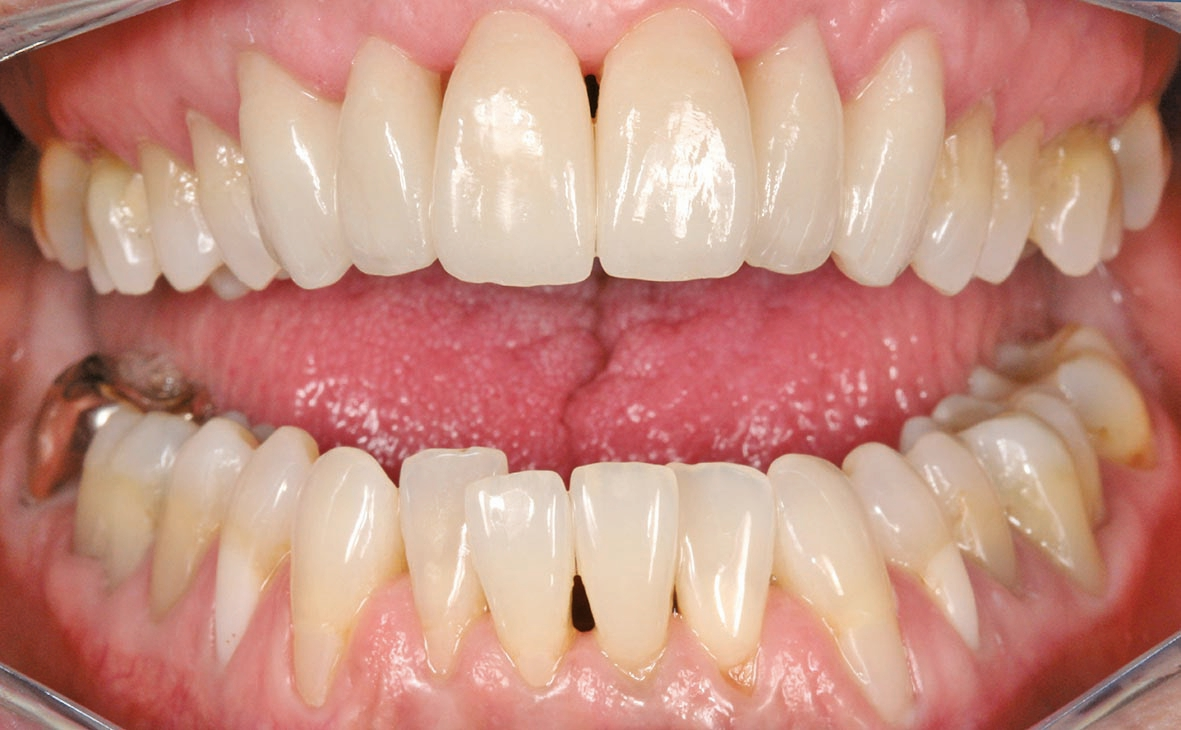

Unsere Patientin stellte sich mit einer starken Parodontitis (Abb. 1a–c) und einer schlechten Mundhygiene in der Praxis von Zahnarzt Andreas Klinkisch (Weidenberg und Bischofsgrün) vor. Am Anfang standen zunächst die Motivation zur besseren Mundhygiene, dann die konkrete Anleitung zum gründlichen Zähneputzen und schließlich die Begleitung der Maßnahmen. Nach diesem Prozess, der fast ein Jahr beanspruchte, stellte sich die 67 Jahre alte Patientin bei mir mit dem großen Wunsch vor, wieder natürliche, ästhetische und etwas hellere Frontzähne mit geschlossenen interdentalen Bereichen zu haben.

Wir sehen uns in derart gelagerten Fällen stets mit mehreren Herausforderungen konfrontiert, vor allem mit diesen: Zum einen müssen die Materialien zuverlässig und robust sein, zum anderen sollen mir die Materialien erlauben, feinste altersspezifische und individuelle Merkmale zu berücksichtigen und „nachzubauen“. Bei dieser Patientin waren die Zähne leicht fluoreszierend, das inzisale Drittel transparent und in der Schneidekante leicht opaleszent. Das Dentin und der Zahnhalsbereich hingegen wirkten stark chromatisch. Auch wollten wir, dass sich das Zahnfleisch bestmöglich an das Material adaptiert. Auch das würde helfen, die schwarzen Dreiecke im Frontbereich zu schließen.